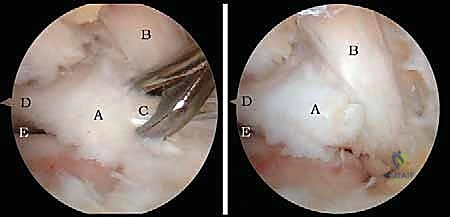

الخطوة 3: الاستكشاف البانورامي (Diagnostic Arthroscopy)

يتم إدخال كاميرا المنظار عالية الدقة (4K) عبر أحد المداخل، بينما تُستخدم الأدوات الجراحية الدقيقة في المدخل الآخر. تتيح الكاميرا للدكتور هطيف رؤية الهياكل الداخلية مكبرة عشرات المرات على شاشة عملاقة، مما يسمح بتقييم دقيق للمفاصل، الأوتار، والأربطة.

الخطوة 4: الإجراء العلاجي الدقيق (Therapeutic Intervention)

بناءً على التشخيص، يتم إجراء العلاج اللازم بدقة متناهية:

* استئصال العظم الزائد (Os Trigonum Excision): يتم فصل العظم الزائد بحذر عن الأنسجة المحيطة واستخراجه بالكامل، مما يزيل سبب الانحشار والألم فوراً.

* تحرير وتنظيف وتر (FHL): إذا كان الوتر ملتهباً ومحاصراً، يتم قطع سقف النفق الليفي لتحريره، وإزالة الأنسجة الملتهبة (Tenosynovectomy) لضمان انزلاقه بحرية.

* إزالة الأجسام الحرة والنتوءات العظمية: يتم التقاط الشظايا العظمية أو الغضروفية وإخراجها، واستخدام أدوات دقيقة (Burr) لتنعيم النتوءات العظمية التي تسبب الاحتكاك.

* معالجة الغضاريف: تنظيف الآفات الغضروفية وتحفيز النخاع العظمي (Microfracture) لتكوين غضروف ليفي جديد.